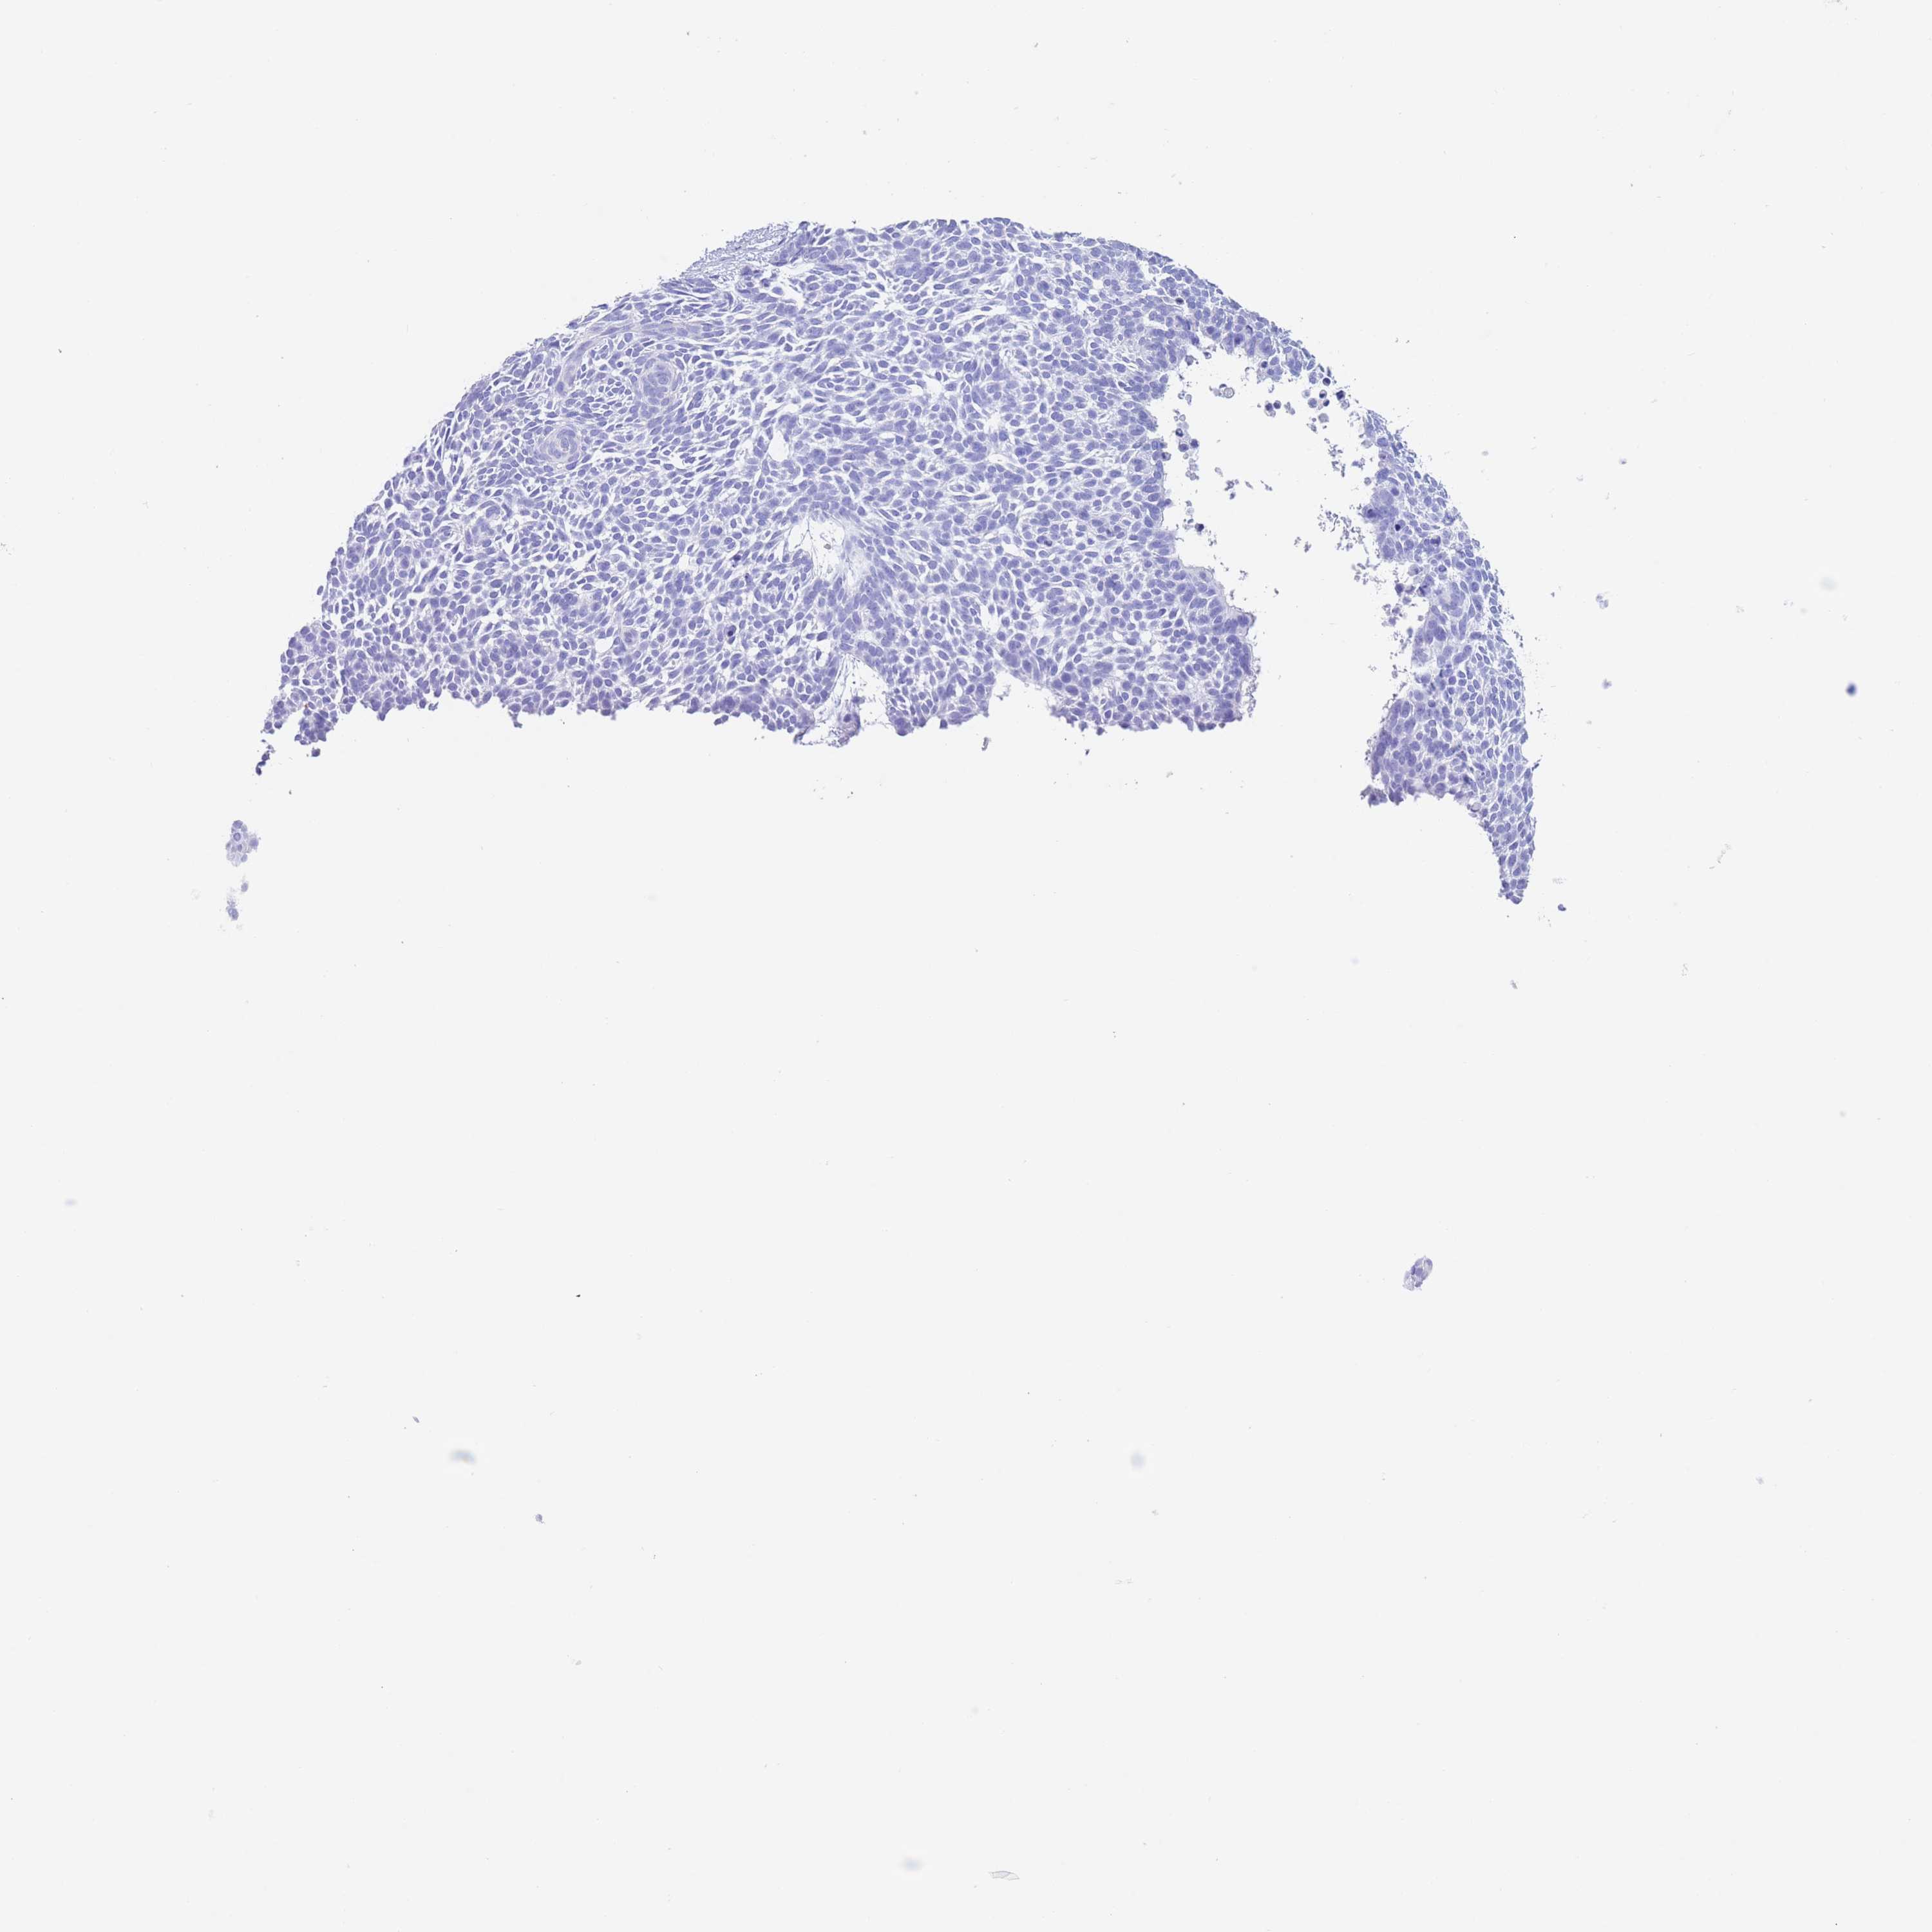

SKIN CANCER - Protein expressioni

A mouse-over function shows sample information and annotation data. Click on an image to view it in a full screen mode. Samples can be filtered based on level of antibody staining by selecting one or several of the following categories: high, medium, low and not detected. The assay and annotation is described here.

Each image is clickable and will lead to virtual microscopy that enables deeper exploration of all samples and also displays staining intensity scores, fraction scores and subcellular localization as well as patient and tissue information for each sample.

Antibody HPA050892

Staining

High

Medium

Low

Not detected

Intensity

Strong

Moderate

Weak

Negative

Quantity

>75%

75%-25%

<25%

None

Location

Nuclear

Cytoplasmic/membranous

Cytoplasmic/membranous,nuclear

Basal cell carcinoma

Squamous cell carcinoma, NOS

Squamous cell carcinoma, metastatic, NOS